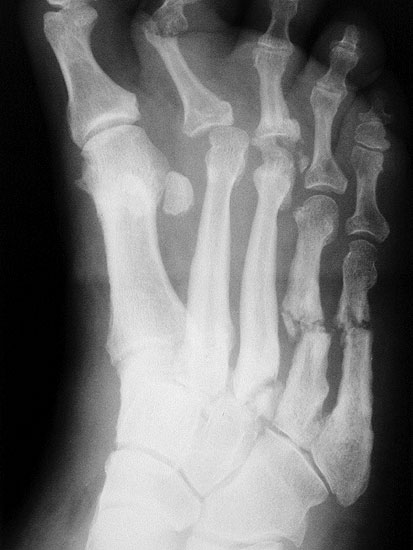

Topographisch wird die diabetisch-neuropathische Osteoarthropathie (DNOAP) in Anlehnung an Sanders (1993) in 5 Typen eingeteilt (Tab. 3).

Tabelle 3: Befallsmuster der diabetischen Neuroarthropathie (DNOAP) nach Sanders (1993)

Typ Befallene Struktur

I Interphalangealgelenke, Metatarso-Phalangealgelenke, Metatarsalia

II Tarso-Metatarsalgelenke

III Naviculo-Cuneiforme-Gelenke, Talonaviculargelenk, Calcaneo-Cuboid-Gelenk

IV Sprunggelenk

V Calcaneus

Abbildung 2

DNOAP Typ I (Abb. 2):

Hierbei handelt es sich um Nekrosen der Interphalangeal-, Metatatarsophalangealgelenke und Metatarsalia, was es zur knöchernen Resorption an den Mittelfußköpfchen und Zehengliedern führt. Die Stummel der Metatarsalia gleichen abgelutschten Zuckerstengeln, bohren sich in der Abstoßphase in die Sohle und führen zum Malum perforans.